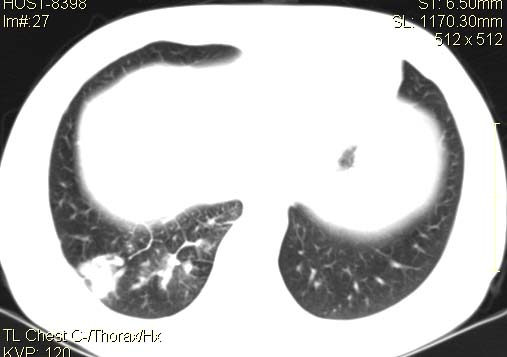

以下是引用qingyuan在2007-4-17 14:19:00的发言:[br]右肺下叶外侧后段胸膜下区节结样病变、分叶、内可见空洞,壁厚薄不均,胸膜凹陷、肺门周围区纹理增粗、僵硬、并近似小结节样改变,肺门区软组织节结、纵膈淋巴结肿大,患者病史长、抗炎治疗无好转炎性改变基本排除,考虑:右肺下叶周围型肺癌伴纵膈及右肺门区淋巴结转移、肺内淋巴管受侵。